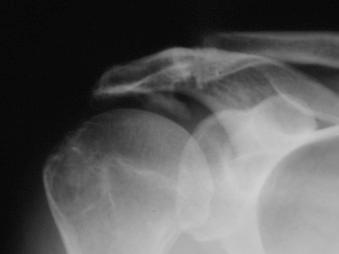

The clinical presentation of patients with full-thickness rotator cuff tears is similar to that of patients with impingement, although complaints of weakness, particularly with overhead activity, may be greater. Plain radiographs are essential to evaluate the shoulder for glenohumeral arthritis, superior migration of the humeral head, acromioclavicular joint arthritis, inferior acromioclavicular joint spurs, and acromial shape. MRI provides information about the size and retraction of the rotator cuff tear and, more important, the degree of atrophy and fatty infiltration of the rotator cuff muscles ( Figs. 12.1–12.5 ).

FIGURE 12.1, Type 3 acromion.

FIGURE 12.2, Anterolateral acromial spur.

FIGURE 12.3, Ossification of the coracoacromial ligament.

FIGURE 12.4, Full-thickness rotator cuff tear.

FIGURE 12.5, Supraspinatus atrophy.